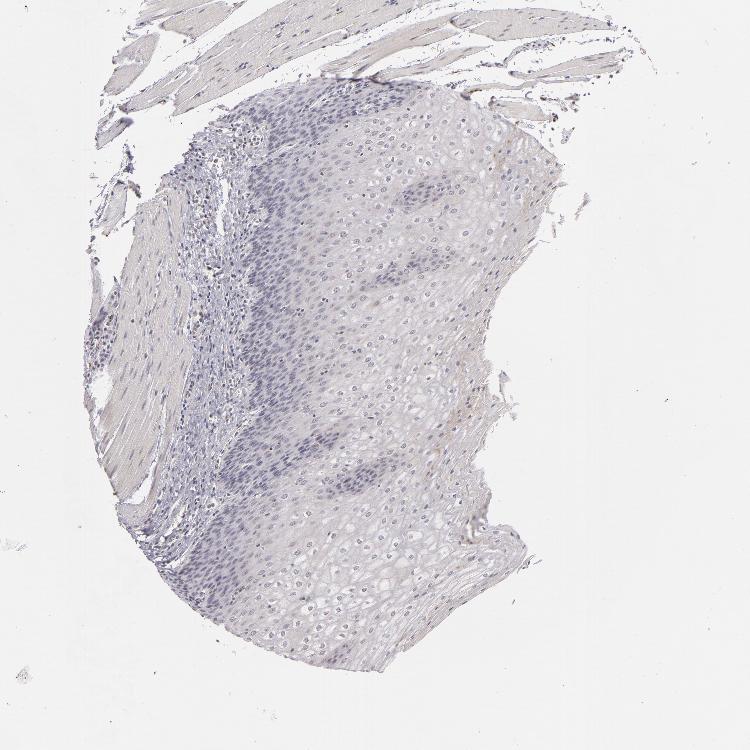

ESOPHAGUS - Antibody stainingi

Antibody staining in the annotated cell types in the current human tissue is reported as not detected, low, medium, or high, based on conventional immunohistochemistry profiling in selected tissues. This score is based on the combination of the staining intensity and fraction of stained cells.

Each image is clickable and will lead to virtual microscopy that enables deeper exploration of all samples and also displays staining intensity scores, fraction scores and subcellular localization as well as patient and tissue information for each sample.

Antibody HPA001586

Squamous epithelial cells Not detected